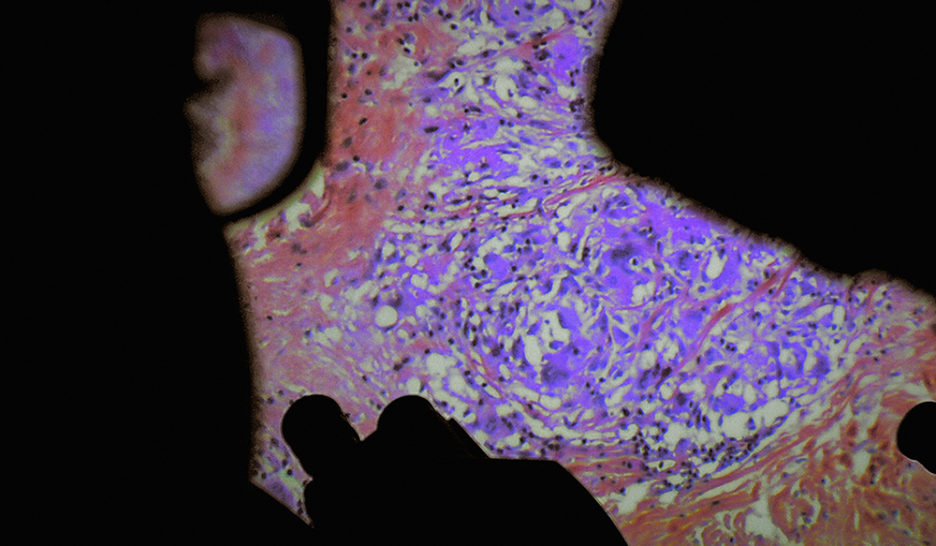

SISTER DISTRIBUTION

En 2013, Véréna Paravel et Lucien Castaing-Taylor avaient marqué les esprits avec Leviathan, immersion sidérante sur un chalutier ­filmée par une dizaine de caméras numériques. Il faut dire que les cinéastes anthropologues, affiliés au Sensory Ethnography Laboratory de Harvard, se démarquent par leur approche singulière, tant sur le fond que la forme. Leurs films, où […]